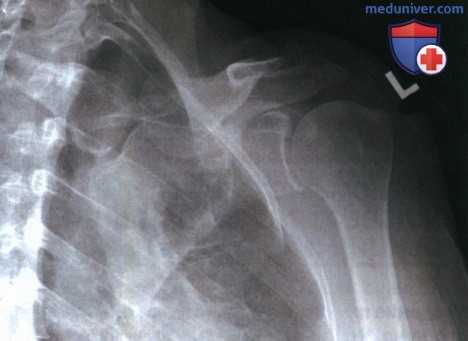

РИСУНОК 3 Рентгенограмма лопатки в ПЗ проекции без отведения плеча. РИСУНОК 4 Рентгенограмма лопатки в ПЗ проекции с недостаточной ретракцией плечевого сустава. РИСУНОК 5 Рентгенограмма лопатки в ПЗ проекции: перелом.

а) Отведение плечевой кости. Плечевая кость отводится в плечевом суставе при ротации лопатки вокруг грудной клетки. Отведение плеча на две трети происходит за счет движения в плечевом суставе, и на одну треть — за счет движения лопатки. При отведении плеча латеральный край лопатки выдвигается из-под грудной клетки, вследствие чего суставная впадина лопатки смещается вверх. Поскольку отведение плеча на первые 60° обеспечивается преимущественно плечевым суставом без сопутствующего движения лопатки, то для отображения всего латерального края лопатки без наложения на него грудной клетки, как и для отображения надостной ямки и верхнего угла лопатки без наложения ключицы, плечевую кость следует отвести как минимум на 90°. Если плечевая кость отведена меньше чем на 60°, нижнелатеральный край лопатки будет накладываться на грудную клетку, а ключица — на верхний угол лопатки (рис. 3).

б) Ретракция плечевого сустава. Если рентгенография лопатки в ПЗ проекции выполняется без отведения плеча на исследуемой стороне, то тело лопатки будет располагаться под углом 35-45° к ПИ, что приведет к его поперечному проекционному укорочению. Чтобы уменьшить выраженность поперечного проекционного укорочения тела лопатки и улучшить его визуализацию, рентгенографию выполняют в положении лежа на спине с отведенной плечевой костью, согнутым локтевым суставом и супинацией кисти за счет наружной ротации плеча (рис. 4).

При отведении плечевой кости лопатка скользит вокруг поверхности грудной клетки, вследствие чего из-под нее выдвигаются нижний угол и латеральный край лопатки. Сгибание локтевого сустава и супинация кисти приводят к ретракции плечевого сустава за счет давления на латеральный край тела лопатки, благодаря чему он смещается назад, что позволяет уменьшить выраженность проекционного укорочения тела лопатки. Чтобы обеспечить максимальную ретракцию плечевого сустава за счет силы тяжести, рентгенографию выполняют в положении лежа на спине. О недостаточном отведении плеча и недостаточной ретракции плечевого сустава свидетельствуют избыточное проекционное укорочение тела лопатки и визуализация суставной впадины лопатки почти в торец (см. рис. 4).